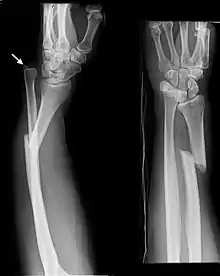

Monteggia Fracture (type of ulna fracture)

Fractures of the ulna can occur at different levels of the bone: near the wrist, in the middle or near the elbow.[2] The fracture may be confined to the ulna or accompanied with damage to the radius or the wrist or elbow joints.[2]